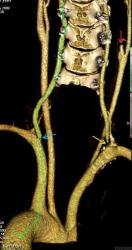

Мужчина, 62 года. Перенес ишемический инсульт в бассейне правой средней мозговой артерии.

На КТ-ангиографии выявлена окклюзия правой внутренней сонной артерии в области развилки в виде паламени свечи (красная стрелка), стеноз высокой степени в устье правой вертебральной артерии (желтая стрелка), небольшой перегиб в устье левой вертебральной артерии (голубая стрелка).